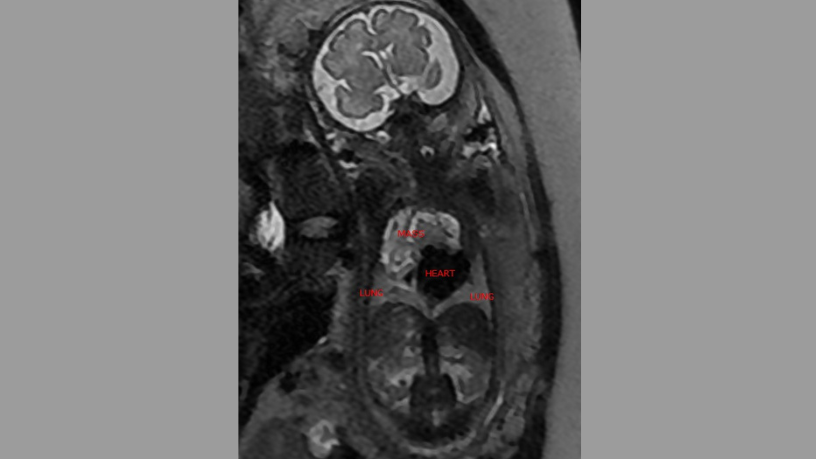

Ao realizar uma nova ultrassonografia e posteriormente a RM fetal, Dra. Thaline Hernandez das Neves Coutinho identificou que a massa não era pulmonar, como inicialmente suspeitado, mas sim localizada no saco pericárdico — estrutura que envolve o coração. A hipótese de uma formação cardíaca foi então discutida com cardiologistas pediátricos e outras especialistas, e, com base nas imagens e achados clínicos, chegou-se ao diagnóstico por imagem de teratoma pericárdico fetal.

A RM fetal se mostrou fundamental para diferenciar o teratoma pericárdico de outras lesões torácicas, como cistos broncogênicos ou linfangiomas. A técnica permitiu observar detalhes como ausência de calcificações e padrão de vascularização, auxiliando no diagnóstico preciso. Com base nesses dados, a equipe multidisciplinar — composta por obstetras, cardiologistas pediátricos, neonatologistas e cirurgiões — elaborou um plano detalhado de parto e tratamento.